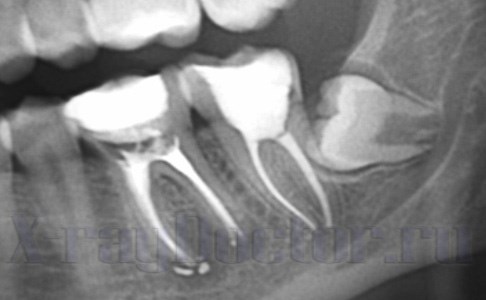

Как увидеть гранулирующий периодонтит на рентгене

Гранулирующий периодонтит на рентгене определяется как наслоение в периапикальной области. При патологии образуются свищи